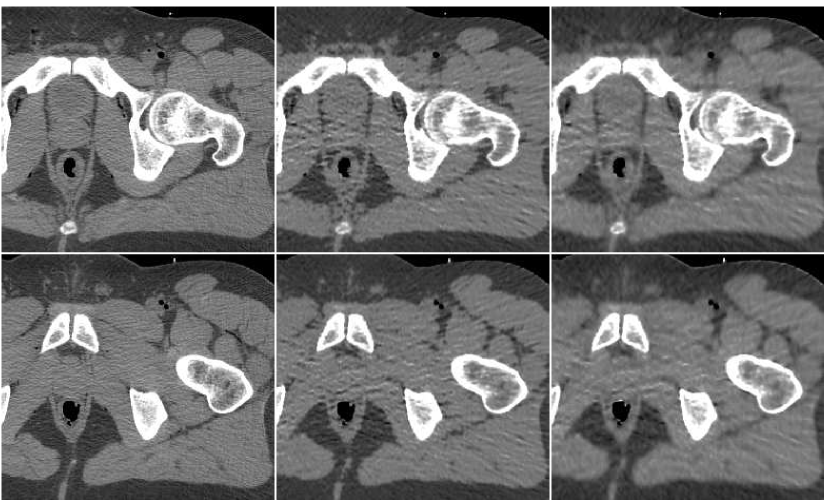

In order to test the robustness of the training results, we apply the ANN trained with the thigh sections, for a reconstruction of images of other body parts – sections of the head and the abdomen. Reconstruction results are presented in Figure 13 in the same order as in the previous comparison: middle image in the upper row is the result of fusion, which components are presented in the lower row. The head reconstruction is improved substantially by the fusion process, as visual observation shows. However, the SNR values (given in Table II) point to the favor of the PWLS image corresponding to iterations (lower middle image). The highest SSIM value does belong to the fusion result, though. In the case of the abdomen section, the fusion image is similar to the -iterations version but contains less noise; its quantitative measures are somewhat better than those of the individual PWLS images.

As a last experiment, we consider the special case where the ANN only performs a local filtering of the single version of the image, without a reference to the other versions. A neighborhood of radius ( pixels) was extracted for each location in the PWLS image, corresponding to iteration number . The fusion result is visually compared in Figure 14 versus the image produced from PWLS versions, as before. It can be observed that the processing by ANN reduces the noise appearing in the PWLS image, but it is slightly inferior to the fusion image produced from several PWLS versions.